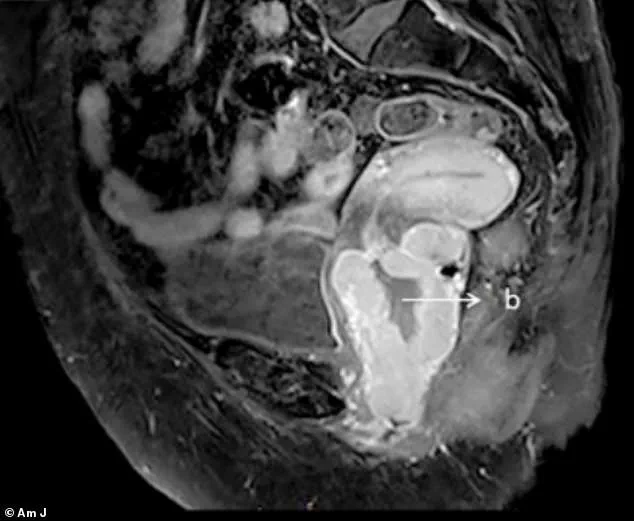

An MRI, shared under strict confidentiality protocols, showed a cervical mass measuring 7.8cm by 5.7cm by 1.0cm, extending into the lower third of the vagina.

Doctors described the lesion as having a 'pigmented appearance,' a characteristic that immediately raised concerns about melanoma.

A biopsy confirmed their suspicion, revealing a malignant melanoma that had already advanced to Stage 4.

The patient reported irregular vaginal bleeding and a strange sensation in her bowels, symptoms that were later confirmed by MRI scans revealing multiple tumors and lesions.